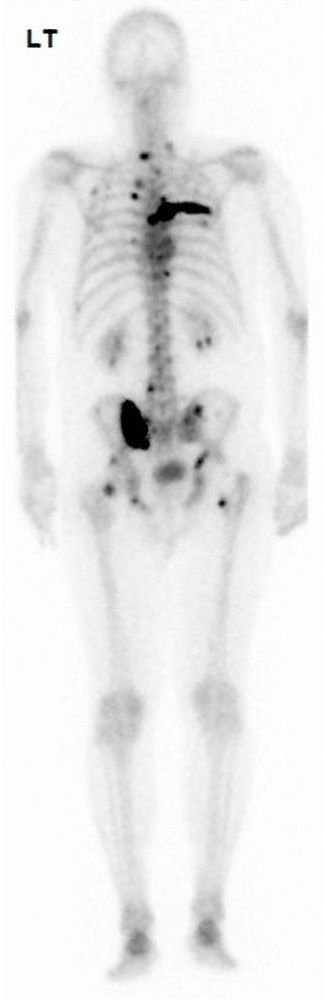

La radiographie thoracique est la suivante :

Figure 2 (Source : Matthieu Roulleaux Dugage)

L’ECBU vous est rendu : leucocytes : 74/mL ; hématies : 6 700/mL ; examen direct : pas de germe au direct ; culture négative.

Les hémocultures vous sont également rendues : hémoculture PAC positive en 4 h à Staphylococcus aureus méti-S sur flacon aérobie et anaérobie ; hémoculture périphérique positive en 7 h à Staphylococcus aureus méti-S sur flacon aérobie et anaérobie.